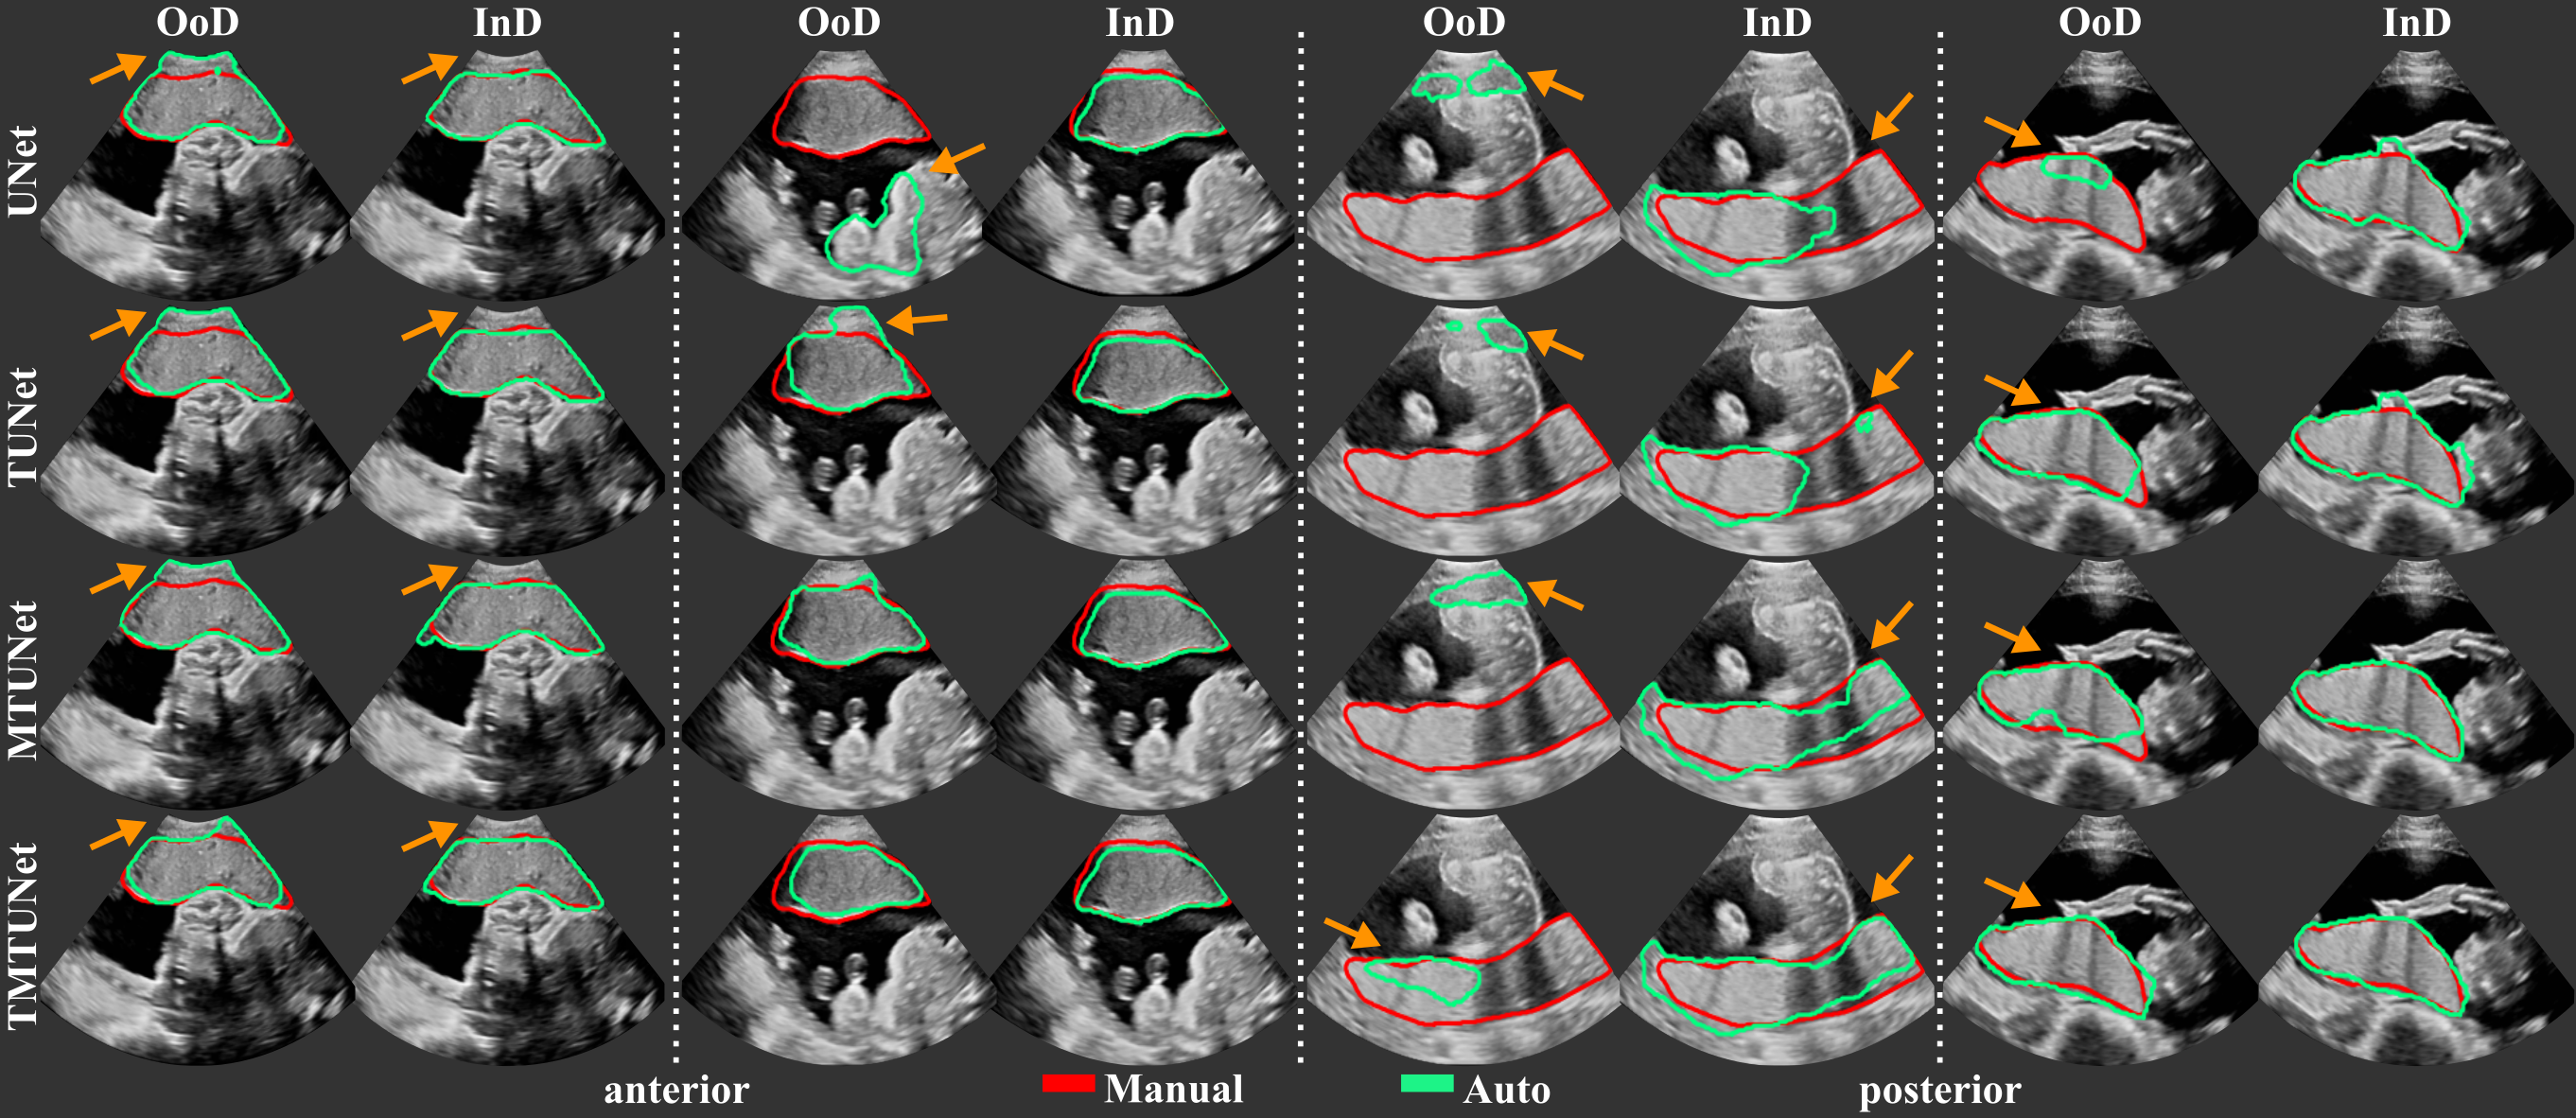

The segmentation performance of the different models measured by Dice, IoU, ASD and RHD are reported in Table 2 and representative segmentations comparing InD and OoD examples are shown in Fig. 4 with further examples in Fig. 11. Results using different training and validation sets suggest that anterior and posterior placentas represent two different distributions in the data. The baseline UNet trained on set A (only anterior) achieves a high Dice score of for the InD test set (anterior), but performs poorly on the OoD set (posterior) with a Dice score of . When trained on set P (only posterior), the Dice score for the InD set (posterior) is , and for the OoD set (anterior). The performance on the OoD sets is reduced with a higher standard deviation, indicating that the sets A and P alone are not representative enough for the segmentation of all types of placenta. These results confirm also that it is easier to segment anterior placentas, which achieve both a higher InD and OoD Dice score. The same trend is observed for the other performance metrics (IoU, ASD, RHD) and models (TUNet, MTUNet, TMTUNet).

With the incorporation of the classification task with additional training data in models TUNet, MTUNet and TMTUNet, the segmentation performances increase on the OoD data (posterior for set A and anterior for set P). In particular, it can be observed that with transfer learning on set A, i.e., the initialization of the encoder weights with EncNet, our method yields a statistically significant (moderate and strong effect size) performance increase from a Dice of (baseline UNet) to (TUNet) and (TMTUNet). The best OoD performance are achieved with model TMTUNet. For the InD data, the additional training data for classification, whose information is incorporated in models TUNet and TMTUNet via weight initialization, is not crucial and the performance increase is not statistically significant. On these data, the best performances are achieved with model MTUNet.

When trained on set AP, which is representative for both anterior and posterior placentas, good performances are achieved on both classes. The multi-task training improves the segmentation results, and this improvement is statistically significant for the measures Dice, IoU and ASD on all classes with model MTUNet, the best performing model.

Notable is that the performance of posterior placentas improve generally more with multi-task learning than the performance of anterior placentas compared to the baseline. As OoD data, posterior placentas improve the Dice score by , while anterior only by with TMTUNet. On the full set AP, posterior improve by with MTUNet, anterior only by .

Figure 4 visualizes examples comparing the segmentation when the images was InD or OoD data. Multi-task models, especially TMTUNet (row 4) show a more robust performance with respect to OoD data. For example, UNet tries to segment a posterior placenta in OoD of example 2 and an anterior placenta in OoD of example 3. Also, MTUNet and TMTUNet are more robust to image artifacts, such as shadows, which is shown in InD of example 3. Further examples can be found in Fig. 11 in the appendix.